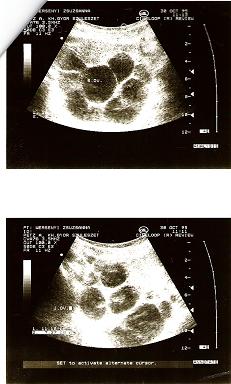

megjöttem a dokitól: "21 mm-es szabályos petezsák, benne embriócsomó (? :shock: :roll: ), szívműködés jelenleg még biztonsággal nem megítélhető." Szóval állítólag olyan a méhem, hogy se nem teljesen hátrahajló, se nem teljesen előrehajló, emiatt a hasi uh-n a beleimtől, hüvelyin a húgyhólyagomtól nem teljesen láthatók a dolgok... Szóval láttunk valami pulzáló valamit, a doki mutatta is, de elég homályos volt. Így azt mondta a doki, nem meri ráírni, hogy megfelelő szívhang, majd jövő héten újra megnézi... :?

Hát nem lettem sokkal nyugodtabb. A petezsákra méret alapján a gép azt dobta ki, hogy 6+3 hetes terhesség. A doki a papíromra azt írta:

Diagnózis: korai graviditas

vélemény: grav. s. 5-6.

Így még egy hét para... :(

Mutatok Neked valamit. A 11 hetes uh-n annyi ciszta volt a hasanban, hogy nem találták meg a babát, csak hosszú küzdelem árán.

Kép

A 14. héten mentem kontrollra, teljesen felszívódott az összes!!!!

Azóta 11 éves a fiam. :D